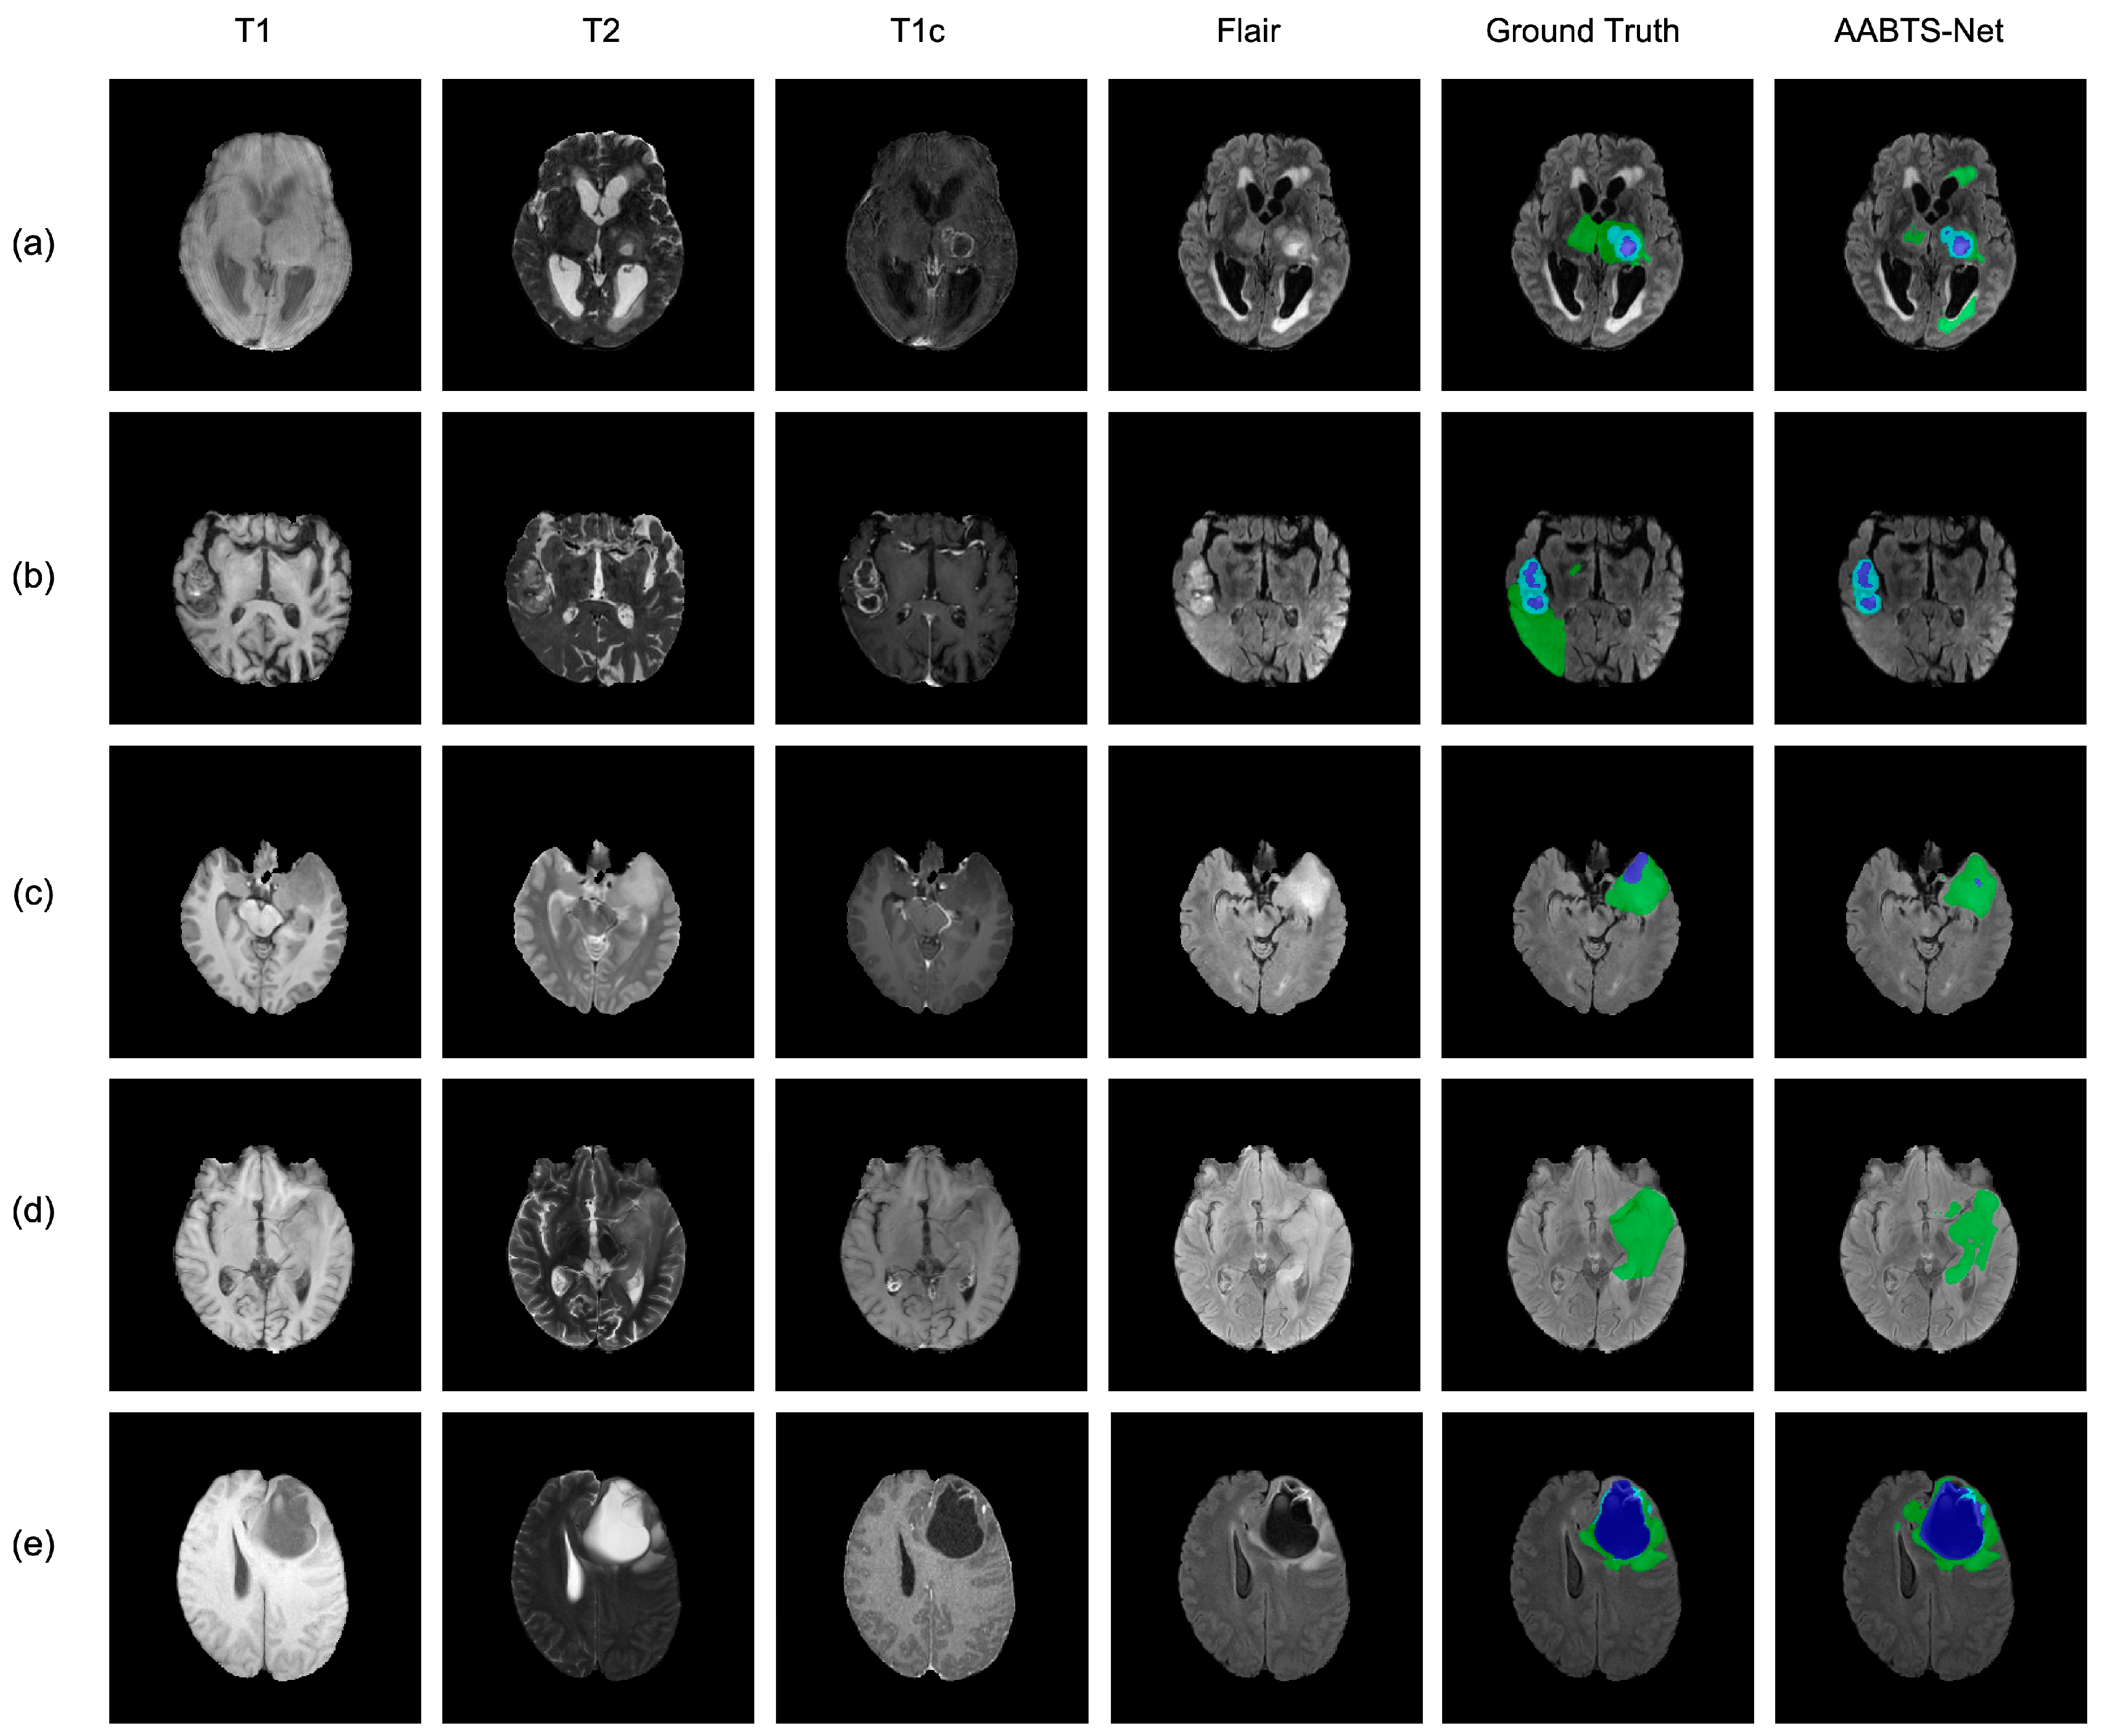

4.3. Analysis of the Bad Tumor Segmentation Results

| Cases | DSC | |||

|---|---|---|---|---|

| ET | TC | WT | AVG | |

| (a) BraTS2021_00493 | 0.885 | 0.924 | 0.270 | 0.693 |

| (b) BraTS2021_00494 | 0.964 | 0.990 | 0.730 | 0.895 |

| (c) BraTS2021_01666 | 0 | 0.738 | 0.916 | 0.551 |

| (d) BraTS2021_01179 | 1.000 | 0 | 0.769 | 0.590 |

| (e) BraTS2021_01293 | 0.541 | 0.929 | 0.874 | 0.781 |